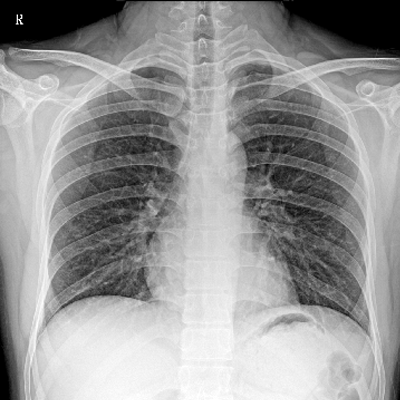

用于影像科、急診室、病房、ICU、手術(shù)室等多場景應(yīng)用。

● 數(shù)字化無線平板成像,操作簡便,成像質(zhì)量高